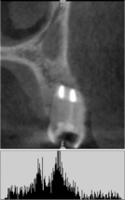

Деминерализованная спонгиоза «Лиопласт»® является рентгенонегативной. Плотность материала, измеренная в первый день после операции РВК (209,08±25,1) оказалась намного меньше плотности здоровой костной ткани (391,25±28,83).

Это объясняется полной декальцинацией этого материала в процессе изготовления и отсутствием в нем минеральных компонентов (рис. 1).

Рис. 1. Гистограмма распределения плотности на дентальной компьютерной томографии фронтального отдела верхней челюсти пациентки О. непосредственно после операции РВК зуба 1.1, 1.2 с заполнением костной полости деминерализованной спонгиозой «Лиопласт»®.